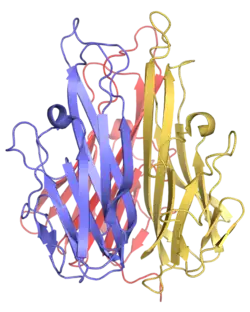

The secreted extracellular portion, denoted sTNF, consists of 157 amino acids.[22] Unlike tmTNF, sTNF can only bind to TNFR1.[10] The secondary structure of sTNF consists primarily of alternating strands that join into two sheets, known as antiparallel β-sheets. The two sheets are layered on top of each other, forming a wedge shape known as an antiparallel β-sandwich. Remarkably, this structure is similar to those seen on the coats of viruses. The last 9 residues of the C-terminus are locked into the middle strand of the bottom sheet, and are necessary for bioactivity.[22]

Both tmTNF and sTNF are only bioactive as homotrimers, whereas individual monomers are inactive.[10] The rate at which TNF trimers disassemble is constant, whereas the rate at which TNF trimers assemble increases with TNF concentration. This causes TNF to be mostly trimers at high concentrations, whereas TNF is mostly monomers and dimers at low concentrations.[23] The coexistence of TNF dimers and trimers in dynamic equilibrium suggests that TNF might be a morpheein.[24] Small molecules that stabilize TNF dimers and prevent the assembly of TNF trimers present a potential mechanism for inhibiting TNF.[25]